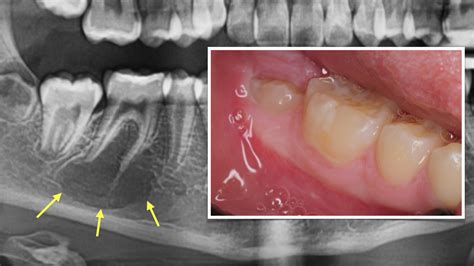

• Infectious Lesions: These are caused by bacterial, viral, or fungal infections. Examples include osteomyelitis and tuberculosis of the bone.

• Infections: Bacterial, viral, or fungal infections can lead to bony lesions. For example, Staphylococcus aureus is a common cause of osteomyelitis.

• bony lesions of the mandible